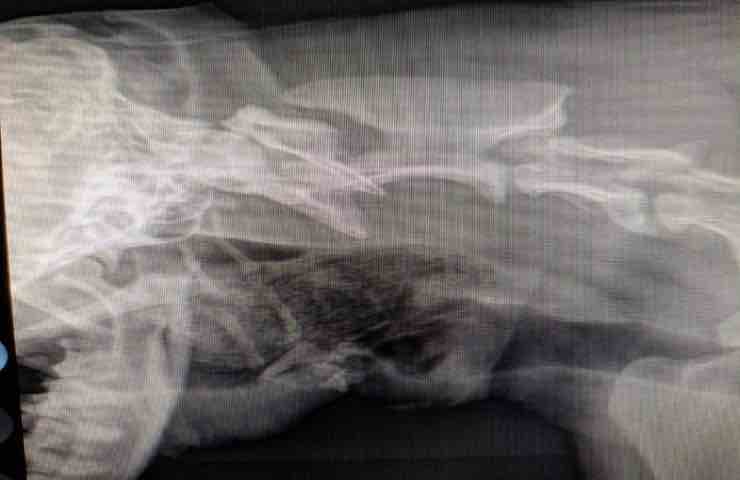

Una donna dopo aver trovato il suo cane mentre rischiava di soffocare, lo porta in un ambulatorio nelle vicinanze, è lì che i veterinari hanno provato in tutti modi a salvare il povero cane, non riuscendoci i medici hanno sedato il cane e hanno deciso di sottoporlo ai raggi X per capire cosa stesse accadendo. C’è da dire che la dottoressa Lauren Jolley e l’infermiera Leanne Boyd, temevano il peggio infatti trattandosi di un cane non più giovanissimo, sospettavano di trovare dei tumori all’interno del petto.

Purtroppo era l’unica spiegazione logica che era venuta in mente alle due donne attraverso la loro esperienza, che ci fosse una malattia che non permettesse più al cane di respirare normalmente. Sono stati minuti molto intensi e dolorosi per la proprietaria del cane ma dopo poco è arrivata la notizia, nella gola del cane non c’erano né noduli, né tumori o altre malattie, ma solo un paio di calzini che lo stavano soffocando.

Dopo aver tirato un respiro di sollievo, la dottoressa ha estratto i calzini dalla gola del cane con l’ausilio di una pinza, inoltre è stato sottoposto anche a tracheostomia, un’incisione chirurgica nella trachea per alleviare un’ostruzione alla respirazione Jip, il cane, stava per morire e non ci sono dubbi, qualche minuto in più e non ce l’avrebbe fatta. Jip è un cane che vive serenamente con Jessica e il suo partner Steven, i due hanno anche una figlia Delilah, il cane è molto amato ed effettivamente ha l’abitudine di masticare oggetti. La dottoressa ha consigliato ai suoi proprietari di fare più attenzione dopo questa traumatica esperienza.